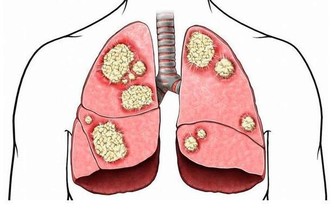

酒精在人體的代謝物——乙醛,攝入量過多,攝入時間過長,必會在人體囤積增加,繼而對許多組織和器官,特別是肝臟,造成極大傷害(進程如圖所示)!